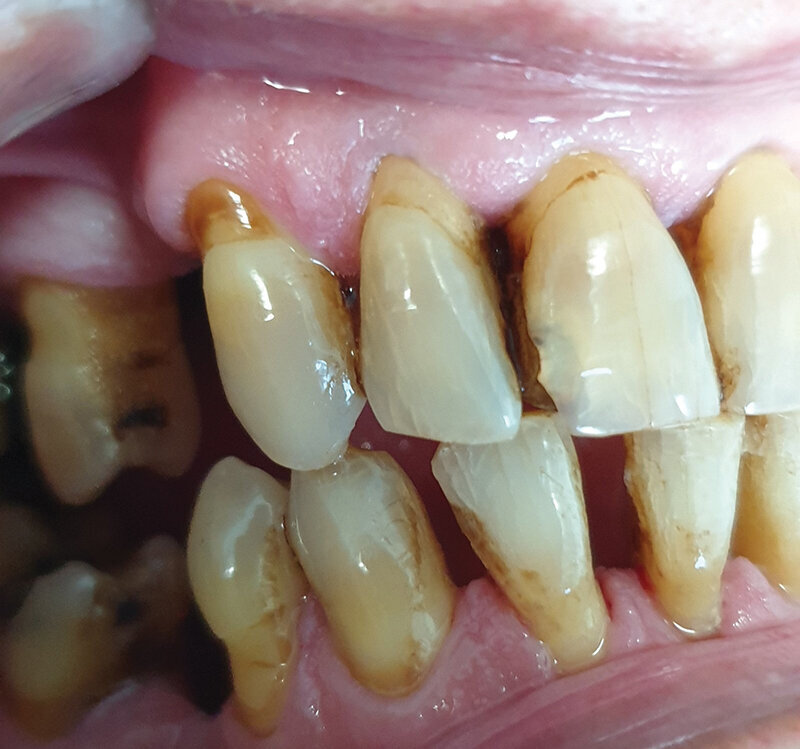

Pacijent B pušač pri prijemu. Estetski neprihvatljive pušačke pigmentacije na svim površinama zuba, naročito onim u estetskoj zoni, direktno izloženim glavnoj struji duvanskog dima. Zubni kamenac i meke naslage ukazuju na nizak nivo oralne higijene. Uočava se i prebojenost kompozitnih aproksimalnih plombi gornjih prednjih zuba. Slabije izražene melanogene pigmentacije desni. Jezik pacijenta takođe je obložen (Sl. 2.0).

Sl. 2.0: Pacijent B, pušač pri prijemu